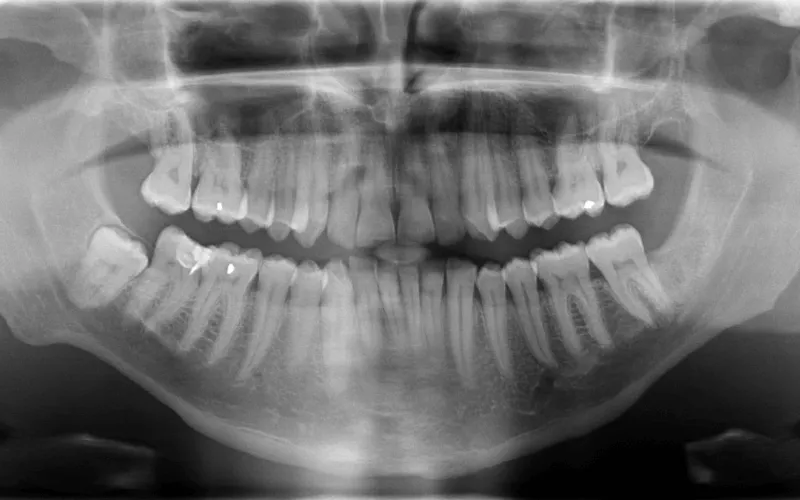

Ortopan slikanje je znano še pod imenoma ortopanthomogram ali panoramsko zobno slikanje, saj lahko z njim zajamemo sliko celotnega zobovja, obeh čeljusti, čeljustnih sklepov, maksilarnih sklepov in obzobnih tkiv. Slika je v 2D obliki, slikanje pa je neboleče in kratko, traja okoli 20 sekund.

2D slikanje zob največkrat uporabljamo v preventivnem zobozdravstvu (kot standardni del pregleda pri novem pacientu za oceno splošnega zobnega zdravja ali pa za oceno rasti in razvoja zob pri otrokih in mladostnikih), pri ocenjevanju rasti modrostnih zob (za določitev njihovega položaja in potencialnih težav, ki bi jih lahko povzročili), pri travmatskih poškodbah (za oceno zlomov ali poškodb čeljusti), v parodontologiji (za oceno izgube kosti zaradi parodontalne bolezni) in ortodontiji (pri odkrivanju položaja in smeri rasti neizraslih ali delno izraslih zob ter načrtovanju ortodontskega zdravljenja).